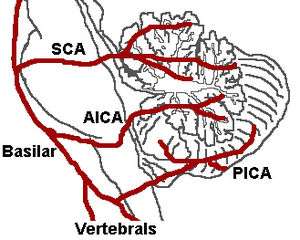

It is the clinical manifestation resulting from occlusion of the posterior inferior cerebellar artery (PICA) or one of its branches or of the vertebral artery, in which the lateral part of the medulla oblongata infarcts, resulting in a typical pattern. The most commonly affected artery is the vertebral artery, followed by the PICA, superior middle and inferior medullary arteries.